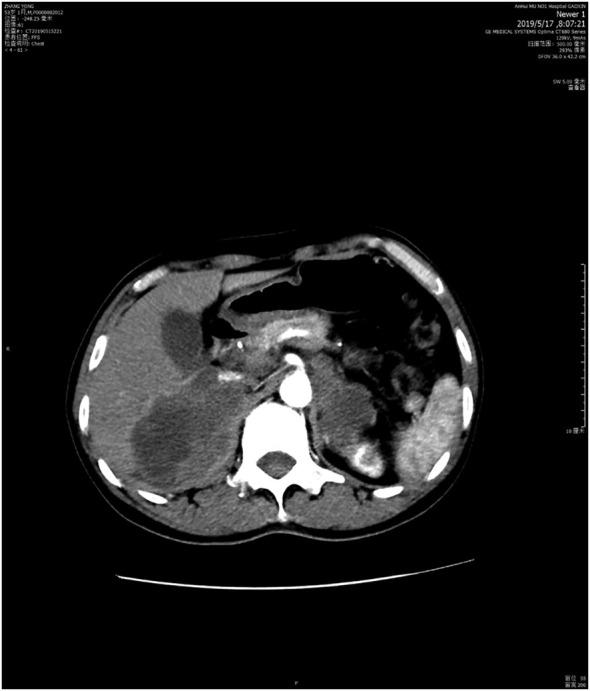

A 53-year-old man diagnosed with disease stage IIIB pulmonary adenocarcinoma underwent chemotherapy and radiotherapy in the first-line setting. After disease progression, he received targeted therapy because of subsequent detection of EGFR exon 19 del mutation. Following an increase in his adrenal metastases, a combination of immunotherapy and antiangiogenic therapy (sintilimab plus bevacizumab) was commenced. After one month, imaging showed that the adrenal metastases had shrunk and a progression-free survival (PFS) of 6.0 months was achieved. In this case, we showed that the PD1 inhibitor sintilimab plus bevacizumab was effective in a refactory advanced EGFR-mutant NSCLC with positive PD-L1 expression. KEY POINTS: Our case report provides clinical evidence of the durable response of a patient with advanced EGFR-mutant lung adenocarcinoma to a combination of immunotherapy and anti-angiogenic agent, sintilimab and bevacizumab, as subsequent-line therapy. Sintilimab and bevacizumab combination therapy was well-tolerated and effective, resulting in dramatic tumor reduction and improvement in clinical symptoms.

一位 53 岁男性被诊断为 IIIB 期肺腺癌,在一线治疗中接受了化疗和放疗。疾病进展后,由于随后检测到 EGFR 外显子 19 缺失突变,他接受了靶向治疗。在肾上腺转移增加后,开始联合免疫治疗和抗血管生成治疗(信迪利单抗联合贝伐珠单抗)。一个月后,影像学显示肾上腺转移缩小,无进展生存期(PFS)达到 6.0 个月。在这种情况下,我们表明 PD1 抑制剂信迪利单抗联合贝伐珠单抗对具有阳性 PD-L1 表达的难治性晚期 EGFR 突变型 NSCLC 有效。关键点:我们的病例报告为晚期 EGFR 突变型肺腺癌患者随后接受免疫治疗和抗血管生成药物信迪利单抗联合贝伐珠单抗联合治疗的持久反应提供了临床证据。信迪利单抗联合贝伐珠单抗治疗耐受性良好,疗效显著,肿瘤明显缩小,临床症状改善。